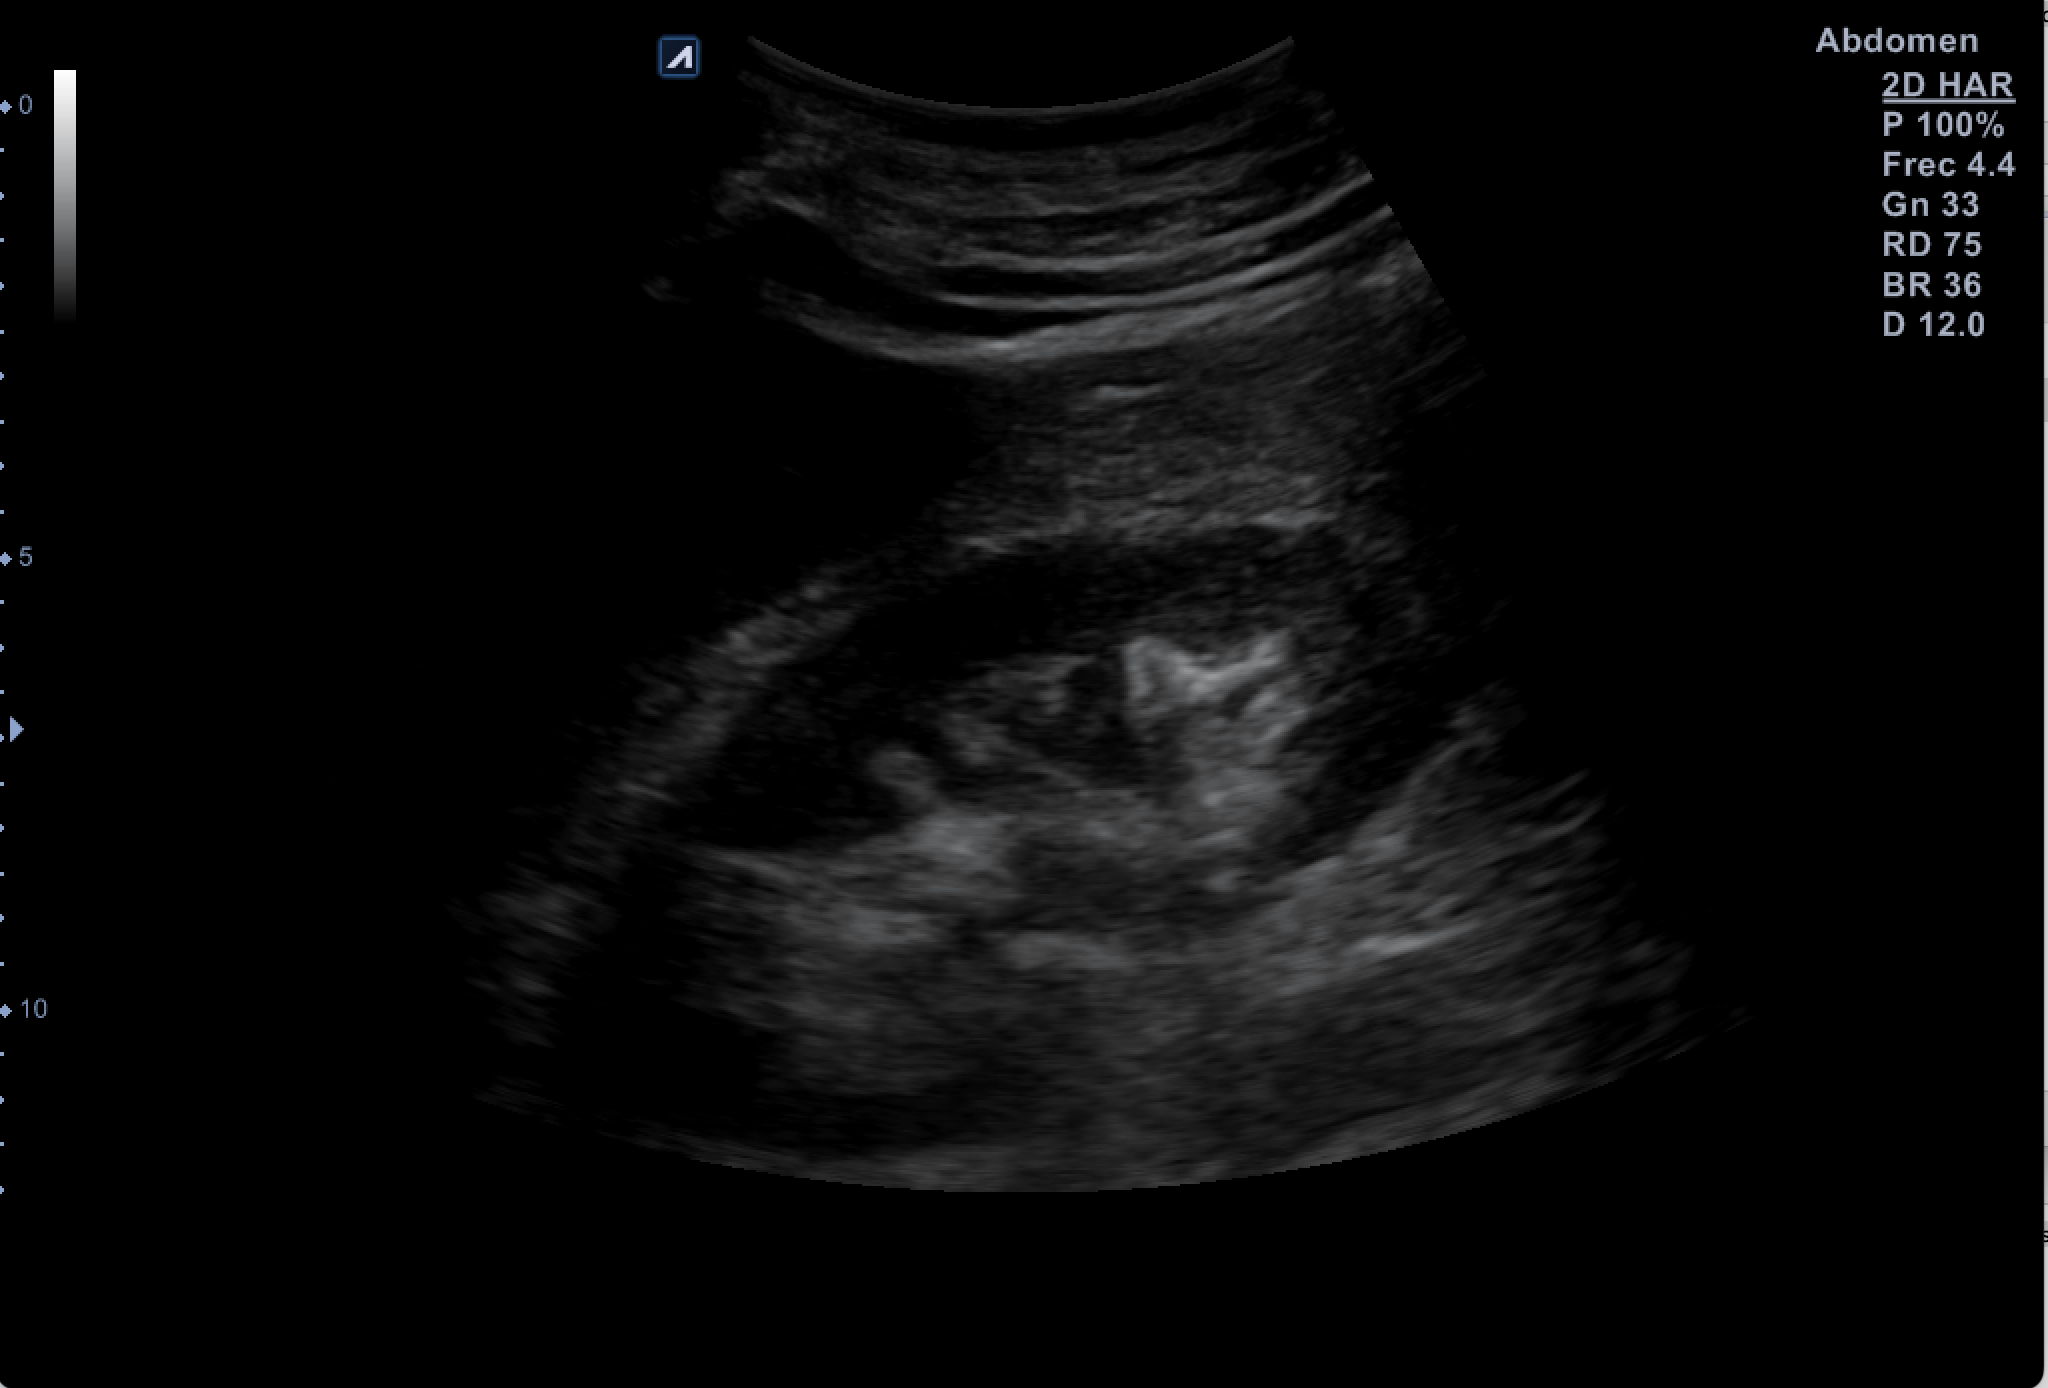

Hallazgos ecográficos

Tras valoración vesicoprostática con vejiga normal, jet vesicales visibles con próstata de 45 cc y residuo postmiccional mínimo. Riñón derecho como normal de tamaño y morfología sin dilataciones pielocaliciales (11 cm de tamaño). El Riñón Izquierdo (RI: 9 cm) presentaba una hidronefrosis grado IV y atrofia cortical con pelvis renal distendida, no consiguiendo detectar la causa obstructiva y considerando la posibilidad de una estenosis de la unión pieloureteral y como segunda opción una litiasis  ureteral pese a la normalidad de los jets vesicales.